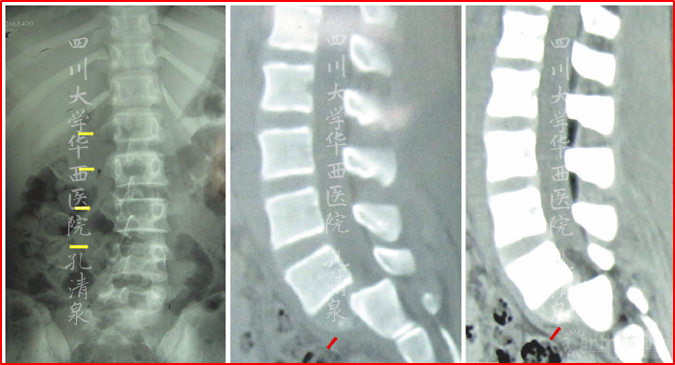

图8 腰椎正位像上示多节段腰椎右侧横突骨折,腰骶部侧凸,CT矢状面重建示腰5椎IV°滑脱,腰5骶1椎间盘完好,骶1前上缘骨骺向前滑移

诊断:1. 腰5创伤性IV°滑脱并骶1骨骺损伤伴脊柱侧凸(SDSG 5型)

2. 腰1-4右侧横突骨折